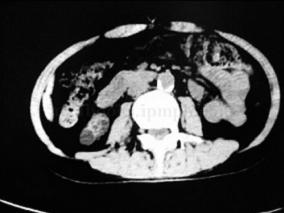

1小时条评论【病例资料】 患者男性,70岁。 主诉:体检B超发现左肾积水10天。 现病史:10天前患者于我院体检,B超提示左肾及左输尿管全长中度扩张积水,左输尿管口黏膜膨出?狭窄?患者无血尿病史,无腰痛、发热,无尿频、尿急、尿痛症状。为进一步诊治于2006年2月22日收入院...